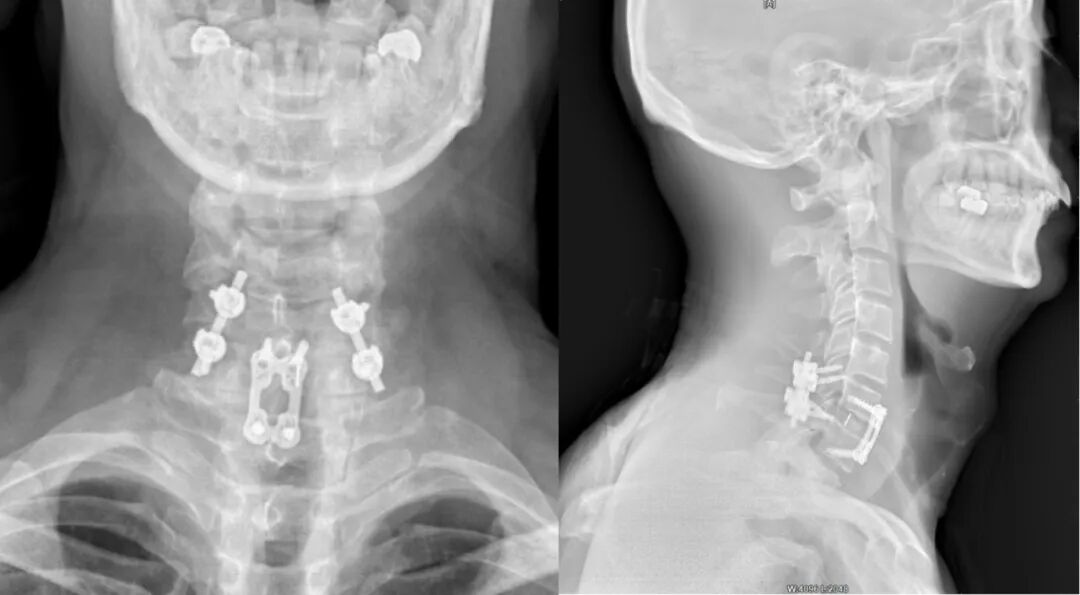

到院后,经过王万垠主任仔细查体及综合影像学检查结果,诊断为:1、颈6骨折脱位并小关节交锁;2、颈髓损伤(ASIA分级C级);3、左胸多发性肋骨骨折并气胸 、肺挫伤;4、左锁骨骨折。“我们先是采取了颅骨牵引,尝试颈椎复位,但患者骨折的位置很特殊,于是又调整了治疗方式。”王万垠主任介绍道。 (术前) 治疗上,王万垠主任组织多学科会诊讨论,并与其家人仔细沟通后,颈部的骨折决定采用“颈后路小关节脱位复位、后路侧块钉棒固定融合术”“颈前路颈6/7椎间盘切除植骨融合内固定术”,术后继续中医药、针灸、理疗康复;“左胸多发性肋骨骨折并气胸 、肺挫伤、左锁骨骨折”由骨三科(正骨科)主任、主任医师李国帅运用“何天佐传统中医药正骨疗法”进行手法复位。经过两周的住院治疗及康复,赵大爷顺利出院。 (术后) “当时听到要手术,我们都非常的担心和焦虑,毕竟他年纪大了,但王主任和周落亮、陈杨帆医生耐心的和我们沟通,也给我们看了很多相似的案例,这才消除了我们的顾虑。”赵大爷家人回忆道。 如今,3个月过去了,赵大爷再次来院复查,经过王万垠主任的仔细查体,发现赵大爷颈、胸、肩痛消失,颈椎及四肢活动度非常好。“真是太感谢王主任了,真是没想到啊,这么短的时间,我能恢复的这么好。”赵大爷激动的说道。